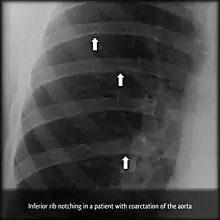

Notching of the ribs (or rib notching) is a radiologic sign where the surface of the rib is deformed. It can be characterized as unilateral or bilateral, and should be differentiated between affecting the upper (superior) or lower (inferior) surface of the rib.

Inferior rib notching can be associated with aortic coarctation (as a result of dilatation of intercostal arteries[1]), superior vena caval obstruction, arteriovenous fistula, or following a Blalock Taussig shunt.